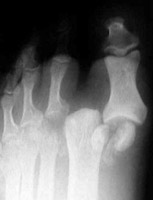

The "turf toe" is the result of a hyperextension injury (such as with soccer or football). This results in avulsion of the capsule and a small fragment of bone from the first metatarsal phalangeal joint. There is also dislocation of the first metatarsal phalangeal joint.

A | AP radiograph of the foot. Image courtesy of Wheeless' Orthopedics. The typical appearance of the turf toe injury. |